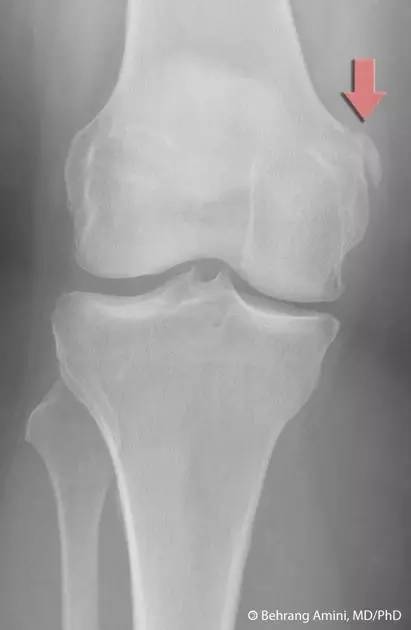

9. Pellegrini-Stieda 损伤

膝关节内侧副韧带附着处的内侧股骨髁的撕脱性骨折。

(来源:radiopaedia)